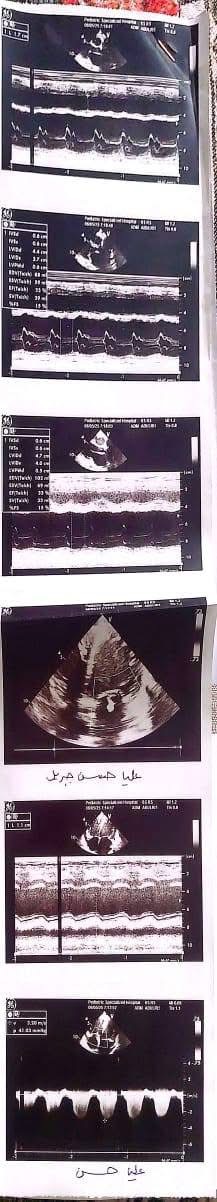

ناشدت أسرة الطفلة عليا حسن، البالغة من العمر أربع سنوات ونصف، الجهات الطبية المعنية وعلى رأسها مؤسسة مجدي يعقوب لأمراض القلب ومستشفى الناس، للتدخل العاجل لإنقاذ حياة ابنتهم، التي تعاني من فشل شديد في عضلة القلب وتضخم كبير بالقلب، ما أدى إلى مضاعفات صحية خطيرة شملت الكبد وأجهزة أخرى من الجسم.

وكشفت أحد أقارب الطفلة تفاصيل الحالة الصحية لها، قائله "عليا حسن بنت خالي 4 سنوات ونصف الأسبوع الماضي جالها استسقاء في معدتها كبير والبنت مكنتش عارفة تتنفس ولا قادرة تتحرك وتعب شديد، لفوا كتير لحد ما عملوا إيكو على القلب وطلع في ضعف شديد في عضلة القلب وتضخم في القلب جامد، ودا طبعا أثر على كل وظائف الجسم وأثر على الكبد بشكل ملحوظ".

وتابعت إحدى أقاربها في منشور لها على الفيسبوك "عليا قعدت في رعاية مستشفى أبو الريش اسبوع، لحد ما كفاءة القلب وصلت ٢٠٪، الحد الأدنى لعمرها ٥٥٪، وخرجت الحمد لله، بس الدكاترة قالوا محتاجة تدخل جراحي سريع لأن حالتها حرجة جدا، محتاجة زرع قلب".